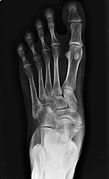

An accessory navicular bone is an accessory bone of the foot that occasionally develops abnormally in front of the ankle towards the inside of the foot. This bone may be present in approximately 2-21% of the general population and is usually asymptomatic.[1][2][3] When it is symptomatic, surgery may be necessary.

Accessory navicular bone may cause a continuous stretch and stress on the tibialis posterior tendon which can progress to chronic disabling pain and may cause tendon rupture or secondary flat foot deformity; when this occurs this condition is commonly known as accessory navicular syndrome.[4]

Diagnosis

To diagnose accessory navicular syndrome, the foot and ankle surgeon will ask about symptoms and examine the foot, looking for skin irritation or swelling. The doctor may press on the bony prominence to assess the area for discomfort. Foot structure, muscle strength, joint motion and the way the patient walks may also be evaluated. X-rays are usually ordered to confirm the diagnosis. If there is ongoing pain or inflammation, an MRI or other advanced imaging tests may be used to further evaluate the condition.[5]